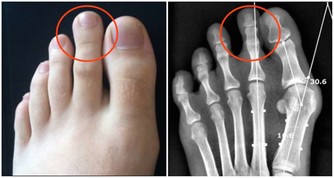

4、疾病困擾

另外,糖尿病、肥胖症以及甲狀腺機能減退等疾病,也可能導致總是睡不醒的症狀發生。